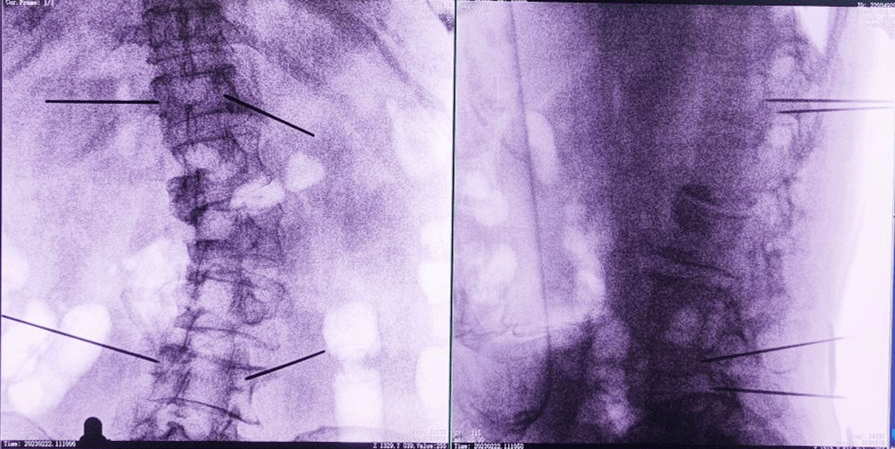

主任為患者注射骨水泥,再次影像掃描后,發(fā)現(xiàn)骨水泥進入位置非常好,彌散效果更佳,手術(shù)順利完成,患者的恢復(fù)也自然更好。

經(jīng)皮椎體成形術(shù),也就是俗稱的“骨水泥手術(shù)”。骨水泥是一種高分子材料,在凝固以前,骨水泥是膠狀的;凝固之后則硬的像骨頭一樣。治療的時候,醫(yī)生首先要在X光的引導(dǎo)下找到病人骨折的脊椎,之后把一根毛衣針粗細的中空穿刺針,通過皮膚穿刺到受損的椎體內(nèi)。